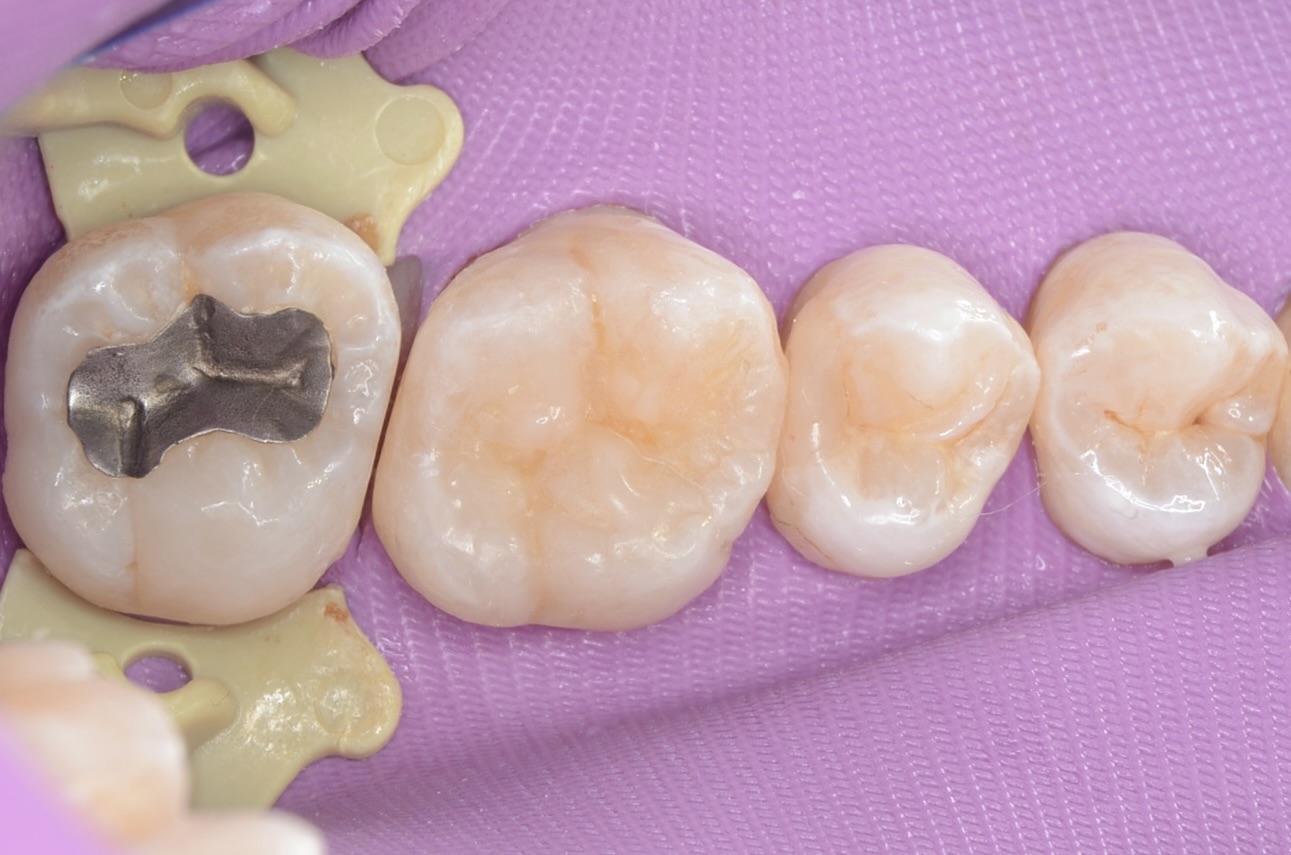

ラバーダム装着

7番のインレーを外します。 -

インレー

インレーの下の虫歯を除去します。 -